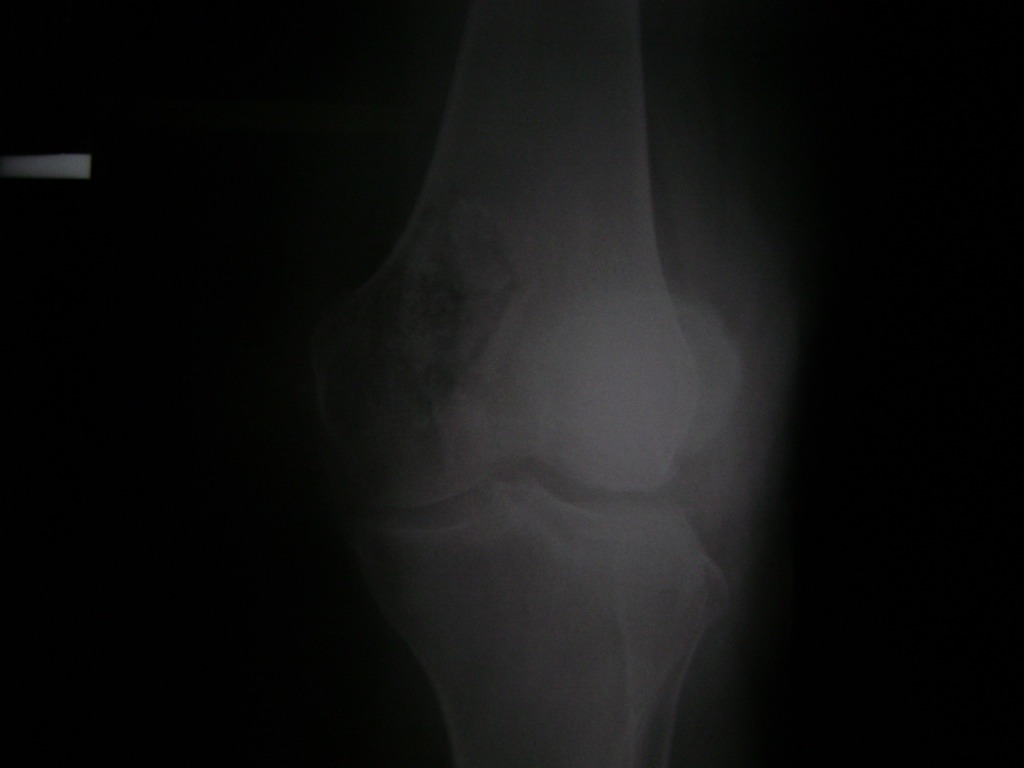

La artroscopia de rodilla es un cirugía en el cual la estructura interna de la articulación es examinada ya sea para realizar un diagnostico o para realizar un tratamiento, este procedimiento se realiza utilizando un instrumento parecido a un pequeño tubo llamado artroscopio.